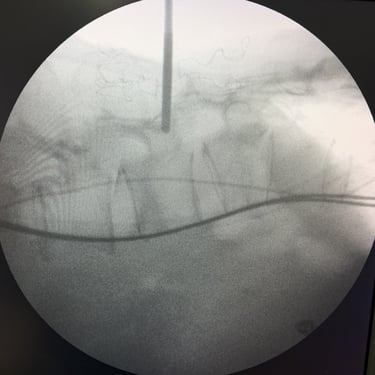

Fractura vertebral lumbar – Artrodesis con tornillos transpediculares (FTP).

La fractura vertebral lumbar es una lesión que puede comprometer la estabilidad de la columna y generar dolor, deformidad o déficit neurológico. En casos seleccionados, el tratamiento quirúrgico mediante artrodesis con tornillos transpediculares (FTP) permite una fijación firme de las vértebras afectadas, restaurando la alineación y brindando estabilidad inmediata. Esta técnica reduce el dolor, previene el desplazamiento vertebral y protege las estructuras neurológicas. La intervención oportuna, junto a una adecuada rehabilitación, favorece una recuperación funcional segura y mejora significativamente la calidad de vida del paciente.